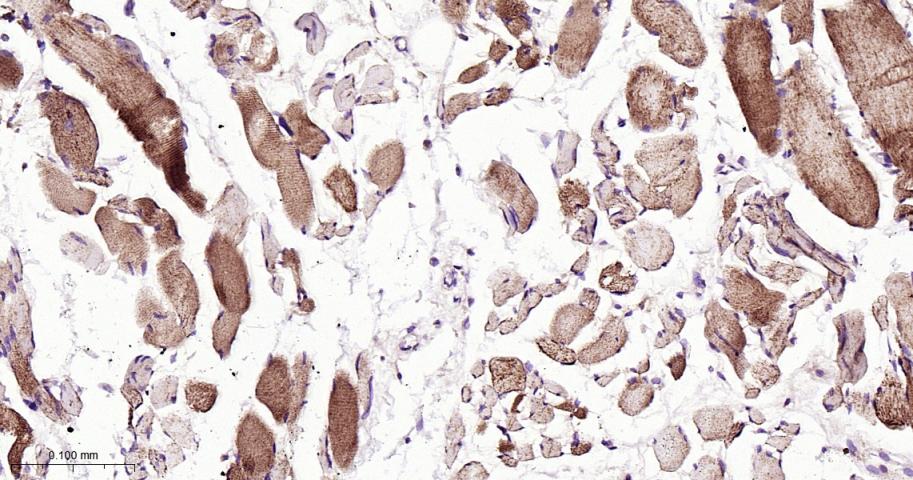

| IHC-P | Human | 1:50-200 | |